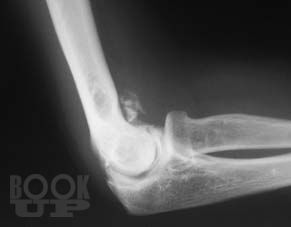

Книга посвящена сложному и разнообразному разделу травматологии – диагностике травматических повреждений крупных суставов у взрослых и детей. Приведены основные рентгеноанатомические сведения о суставах. Дана рентгенологическая характеристика разнообразных повреждений костей и мягких тканей, доступных рентгеновскому исследованию. Представлена рентгенологическая картина посттравматических, в том числе послеоперационных воспалительных осложнений – артритов.